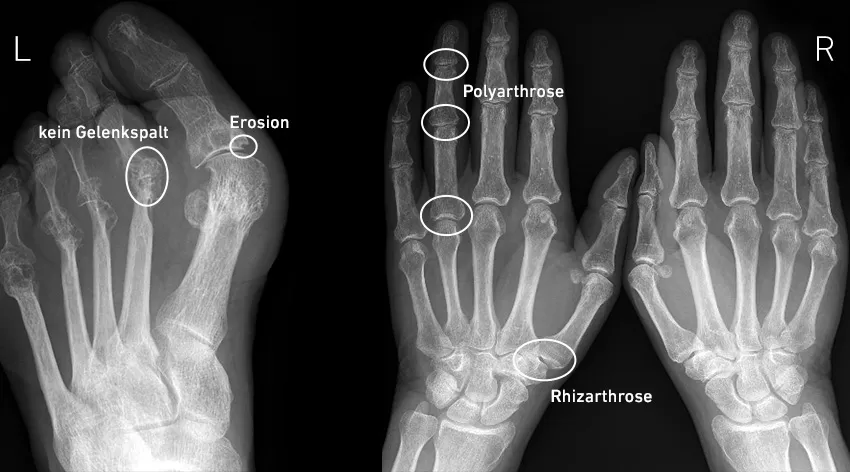

- Bildgebende Verfahren wie Röntgen, Ultraschall und MRT sind entscheidend für die Früherkennung und Verlaufskontrolle der Erkrankung.

Bildgebende Verfahren: Früherkennung und Verlaufskontrolle von Rheuma

Bildgebende Verfahren sind entscheidend für die Diagnostik und Überwachung von rheumatoider Arthritis. Diese Techniken ermöglichen es Ärzten, strukturelle Veränderungen in den Gelenken frühzeitig zu erkennen und den Verlauf der Erkrankung zu beobachten. Zu den gängigsten bildgebenden Verfahren gehören Röntgenaufnahmen, Ultraschalluntersuchungen und die Magnetresonanztomografie (MRT). Jedes dieser Verfahren hat seine eigenen Vorteile und Anwendungen, die in der Diagnostik von rheumatoider Arthritis von großer Bedeutung sind.

Röntgenaufnahmen sind hilfreich, um Gelenkveränderungen wie Knochenschäden zu erkennen, die oft erst in späteren Krankheitsstadien sichtbar werden. Ultraschalluntersuchungen hingegen bieten den Vorteil, dass sie entzündliche Veränderungen an Knorpel und Sehnen frühzeitig erfassen können. Die MRT ist besonders sensitiv und kann selbst kleinste entzündliche Veränderungen darstellen, was sie zu einem wertvollen Instrument in der frühen Diagnostik macht. Diese bildgebenden Verfahren tragen dazu bei, eine präzise Diagnose rheumatoider Arthritis zu stellen und den Krankheitsverlauf effektiv zu überwachen.

Röntgen, Ultraschall und MRT: Unterschiede und Nutzen

Die unterschiedlichen bildgebenden Verfahren bieten jeweils spezifische Vorteile. Röntgenaufnahmen sind kostengünstig und weit verbreitet, zeigen jedoch oft erst in fortgeschrittenen Stadien Veränderungen. Ultraschall ermöglicht eine dynamische Untersuchung und ist ideal, um entzündliche Veränderungen in Echtzeit zu erfassen. Im Gegensatz dazu bietet die Magnetresonanztomografie (MRT) eine detaillierte Ansicht der Weichteile und kann frühe entzündliche Veränderungen sichtbar machen, ist jedoch teurer und zeitaufwändiger. Jedes Verfahren hat seine Stärken und Schwächen, die bei der Auswahl der geeigneten Diagnosetechnik berücksichtigt werden sollten.

Bildgebende Diagnostik: Wie sie den Krankheitsverlauf zeigt

Die fortlaufende bildgebende Diagnostik spielt eine wesentliche Rolle bei der Überwachung der rheumatoiden Arthritis. Regelmäßige Röntgen- und MRT-Untersuchungen ermöglichen es Ärzten, den Fortschritt der Erkrankung zu verfolgen und die Wirksamkeit der Therapie zu bewerten. Veränderungen in den Bildern können auf eine Verschlechterung oder Verbesserung des Zustands hinweisen und helfen, die Behandlungsstrategien anzupassen. Eine kontinuierliche bildgebende Diagnostik ist somit entscheidend, um Gelenkschäden zu verhindern und die Lebensqualität der Patienten zu erhalten.

- Röntgen: Ideal zur Erkennung von Knochenschäden in späteren Stadien

- Ultraschall: Nützlich für die frühzeitige Erfassung von Entzündungen

- MRT: Bietet detaillierte Informationen über Weichteile und frühe entzündliche Veränderungen